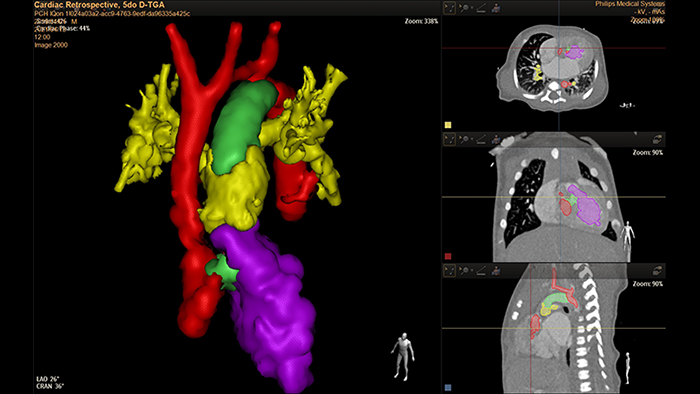

Análise D-TGA de 5 dias com HeartNavigator